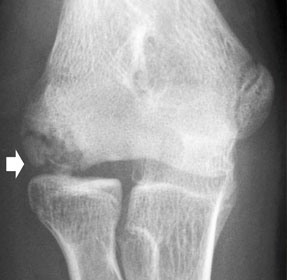

2.自家骨軟骨移植法(モザイクプラスティー)

膝関節の中でも後遺症を残しにくい部分(大腿骨滑車部)から、自分の正常な軟骨を骨ごと採取し、これを膝関節や肘関節の軟骨が損傷した部位に移植する方法です。